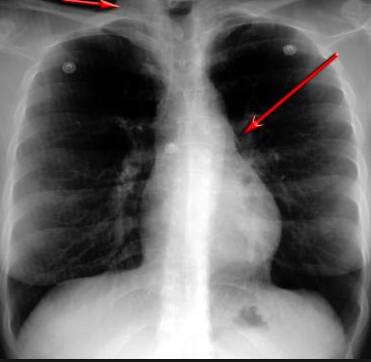

并且,因為呼吸系統結構復雜,在體檢時醫生很難通過一種檢測手段,判定早期患者的病情。

把整個肺部看得清清楚楚!

使用這臺掃描儀,將直接把器官變成3D圖形!細微的毛細血管,幾毫米大的肺泡和支氣管,都將能看的一清二楚!

你的每一個氣泡,每一段支氣管,哪兒有病變都清清楚楚的將展示在醫生面前!

也就是說在一切都還沒開始惡化前,把這些有問題的器官組織都暴露的一清二楚:

沒有這項新技術,醫生在做體檢的時候,很難通過一種測試斷定一個人是否有呼吸系統疾病。

可是現在他們不但能看到整個肺部的3維結構圖。還能看到空氣進入人體后的所有微小變動!